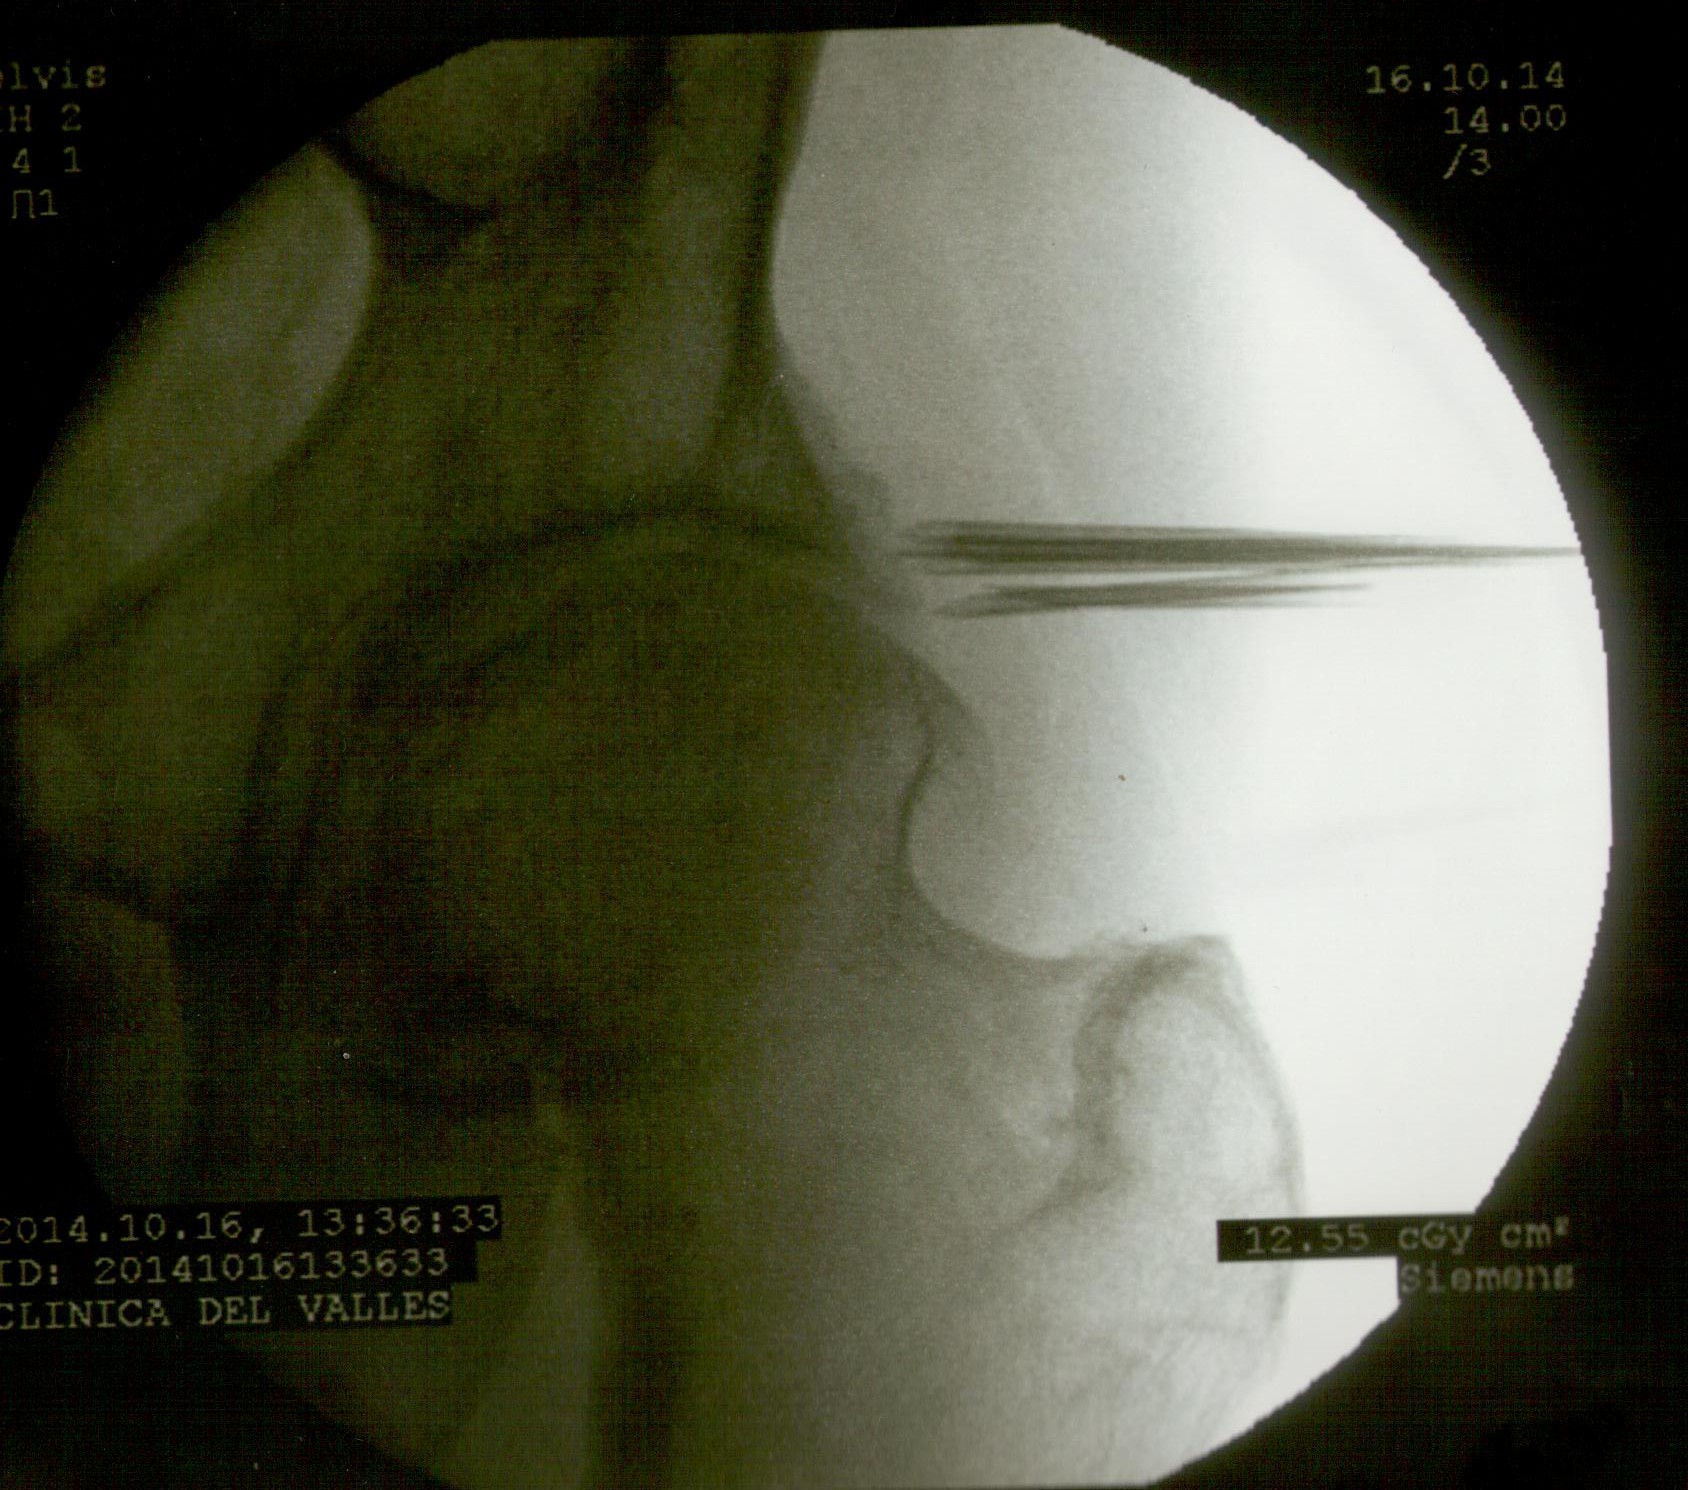

A continuación las imágenes de radioscopía que corresponden al paciente en cuestión. Se observan en primer lugar la colocación de las agujas que vehiculizan los microimplantes, y éstos (pequeños puntos) ubicados próximos a la ceja cotiloidea y a la osteofitosis de la cabeza del fémur.